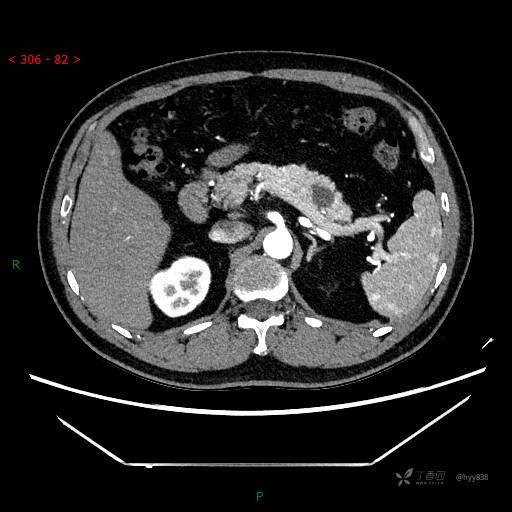

静脉期